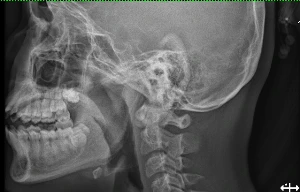

TPO - Bé gái 13 tuổi nhập viện trong tình trạng nuốt vướng, đau nhiều phần hạ họng sau khi ăn thịt gà. Nguyên nhân do bệnh nhi nuốt phải đoạn xương gà lớn, sắt nhọn khi vừa ăn vừa xem tivi.